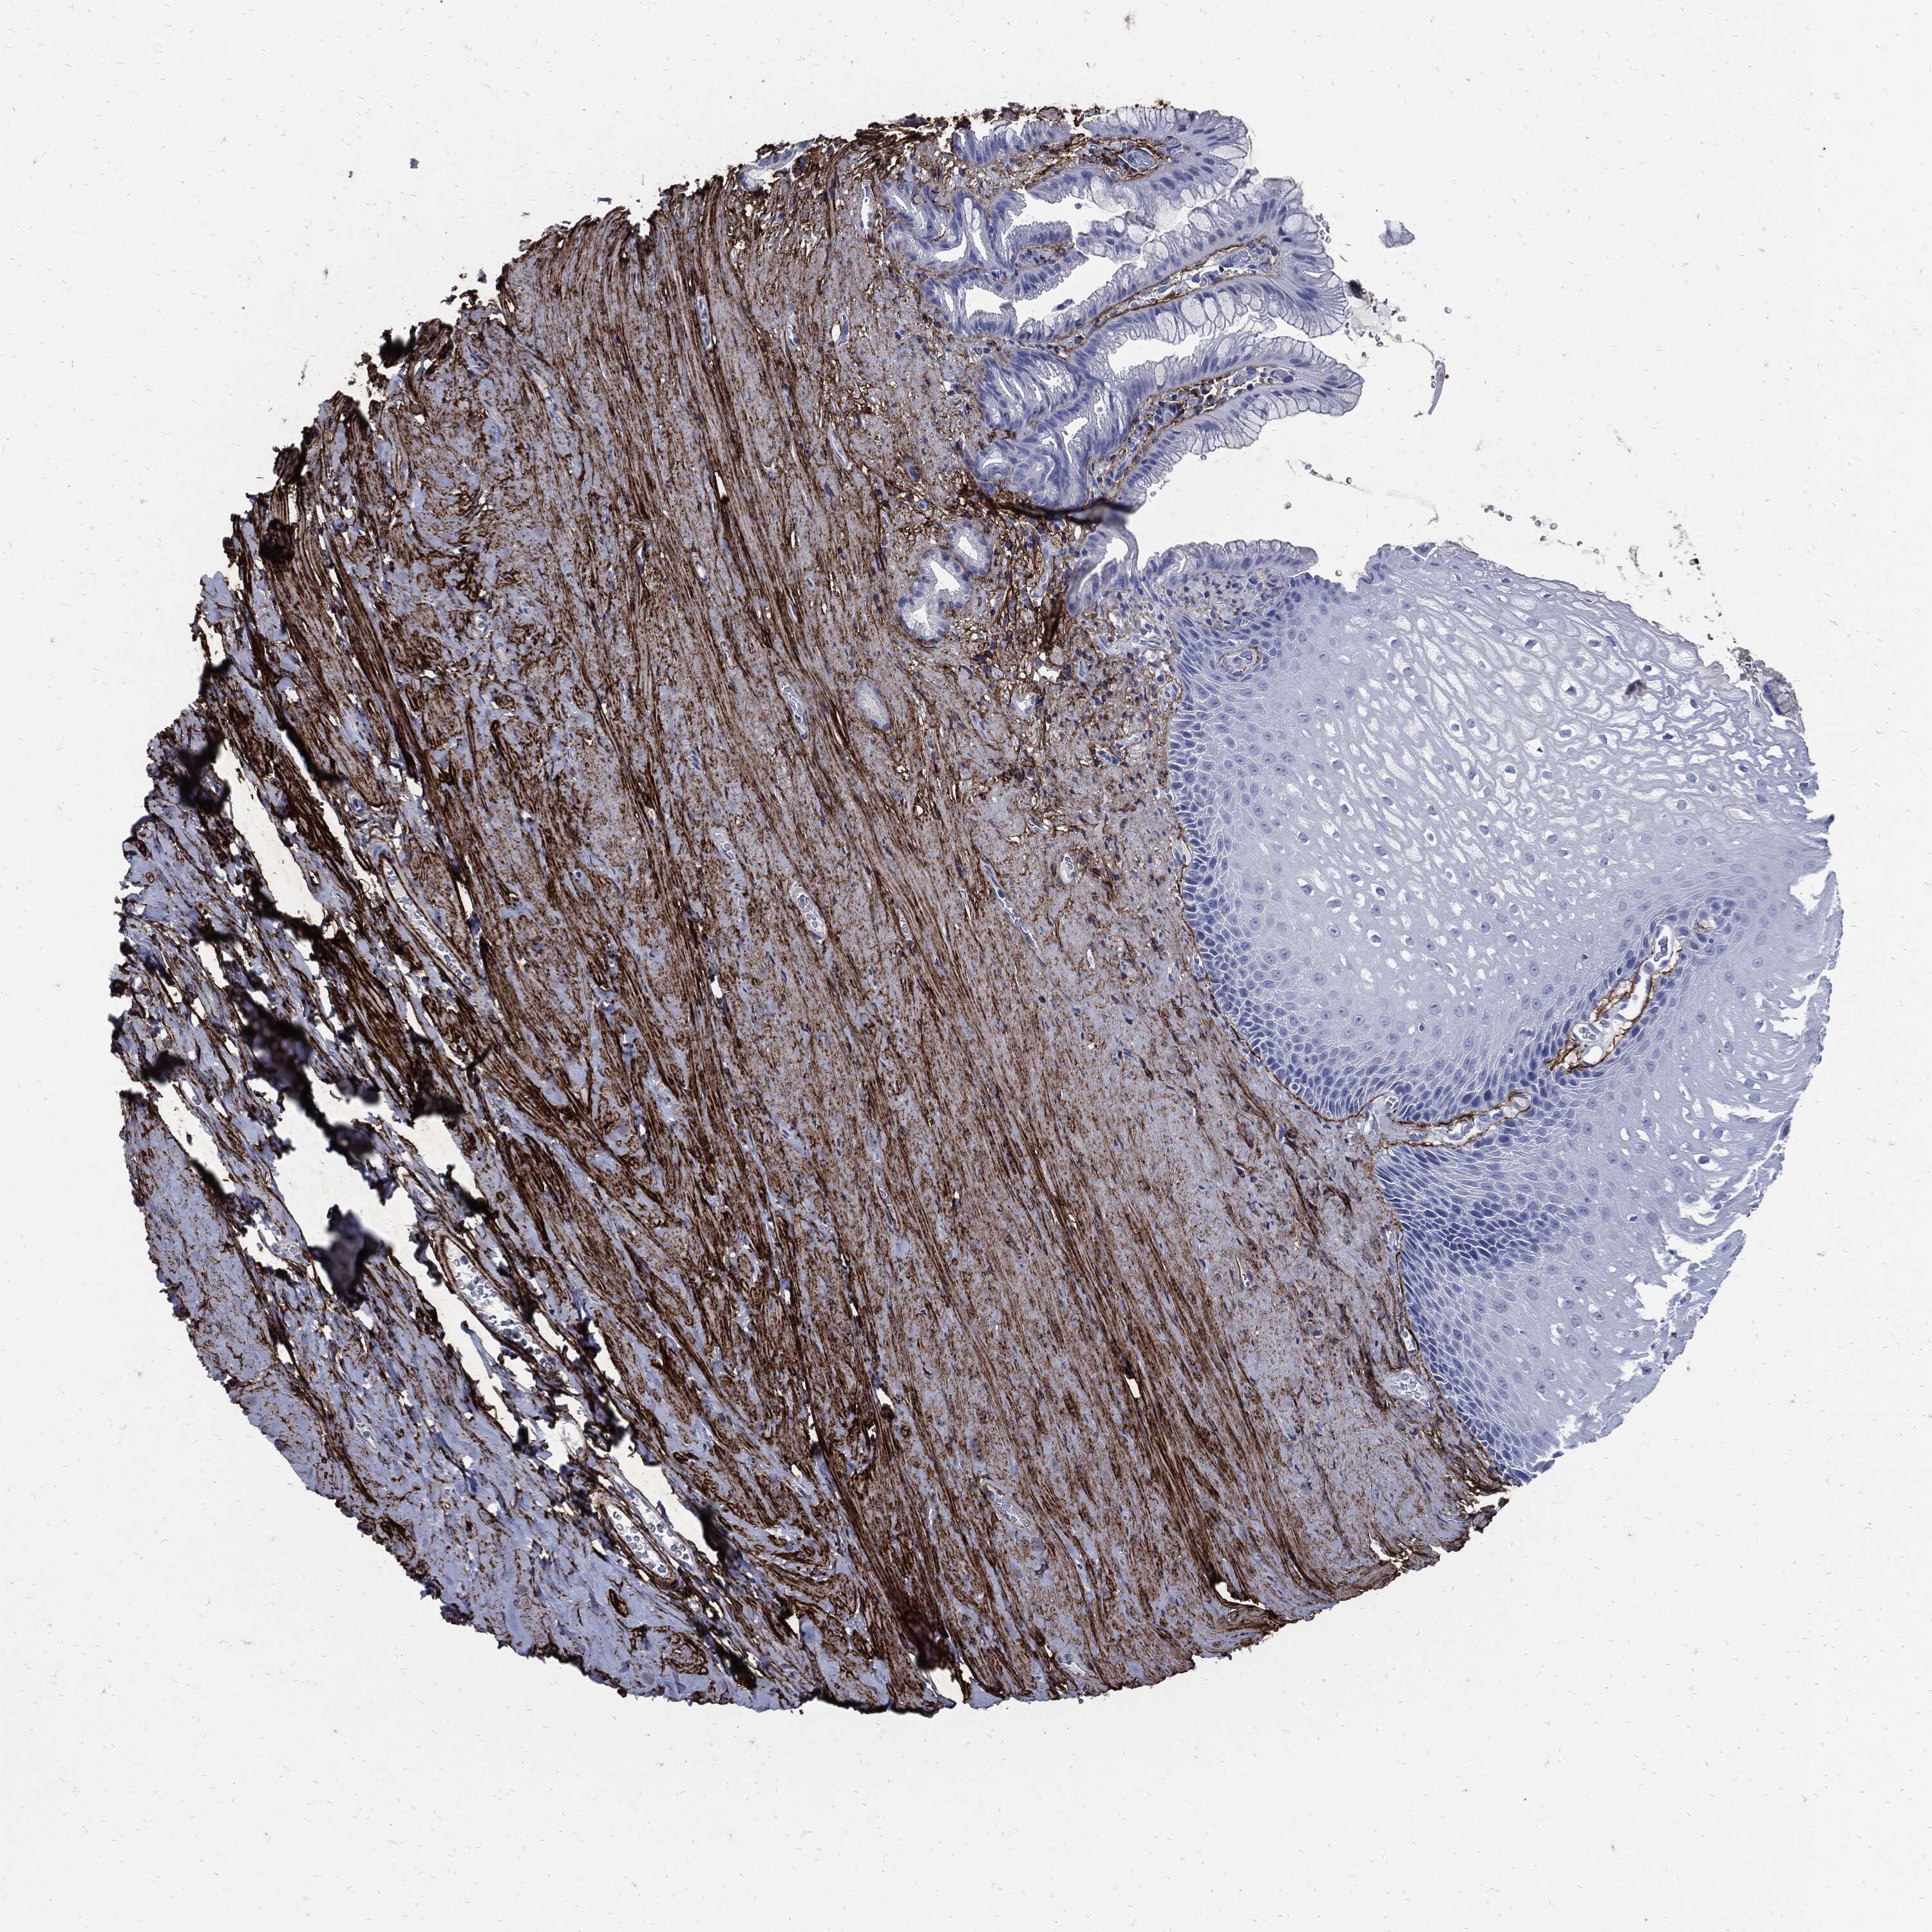

ESOPHAGUS - Antibody stainingi

Antibody staining in the annotated cell types in the current human tissue is reported as not detected, low, medium, or high, based on conventional immunohistochemistry profiling in selected tissues. This score is based on the combination of the staining intensity and fraction of stained cells.

Each image is clickable and will lead to virtual microscopy that enables deeper exploration of all samples and also displays staining intensity scores, fraction scores and subcellular localization as well as patient and tissue information for each sample.

Antibody HPA017759Antibody HPA021057Antibody CAB002670Antibody CAB058696Antibody CAB068188Antibody CAB080202

Squamous epithelial cells Not detectedNot detectedNot detectedNot detectedNot detectedNot detected